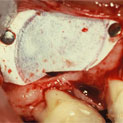

Es una intervención sencilla, que se asocia a la colocación del implante en los casos en los que el hueso no es lo suficientemente ancho como para que el implante quede rodeado por el mismo en su totalidad.

En algunos casos se regenera en el momento de la extracción del diente, para preparar mejor el hueso, dejándolo cicatrizar durante un tiempo hasta la puesta del implante. En otros, es en el momento de la colocación del implante cuando recurrimos a la regeneración del hueso perdido.